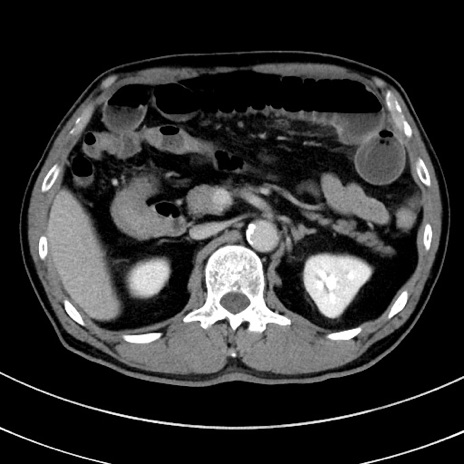

症例8(横断像)

【症例】 60歳代男性

【主訴】 黒色吐物

【現病歴】 4日前から嘔気自覚、2日前の朝食後にも嘔気あり、自分で手で嘔吐反射起こし嘔吐したところ血が混ざっていたため受診。

【既往歴】 5年前汎発性腹膜炎を伴う急性虫垂炎で手術、高血圧、前立腺肥大症、高脂血症

【身体所見】 腹部正中に手術癩痕あり 腹部平坦・軟圧痛なし膨満感あり

【データ】WBC 8400、CRP 4.54